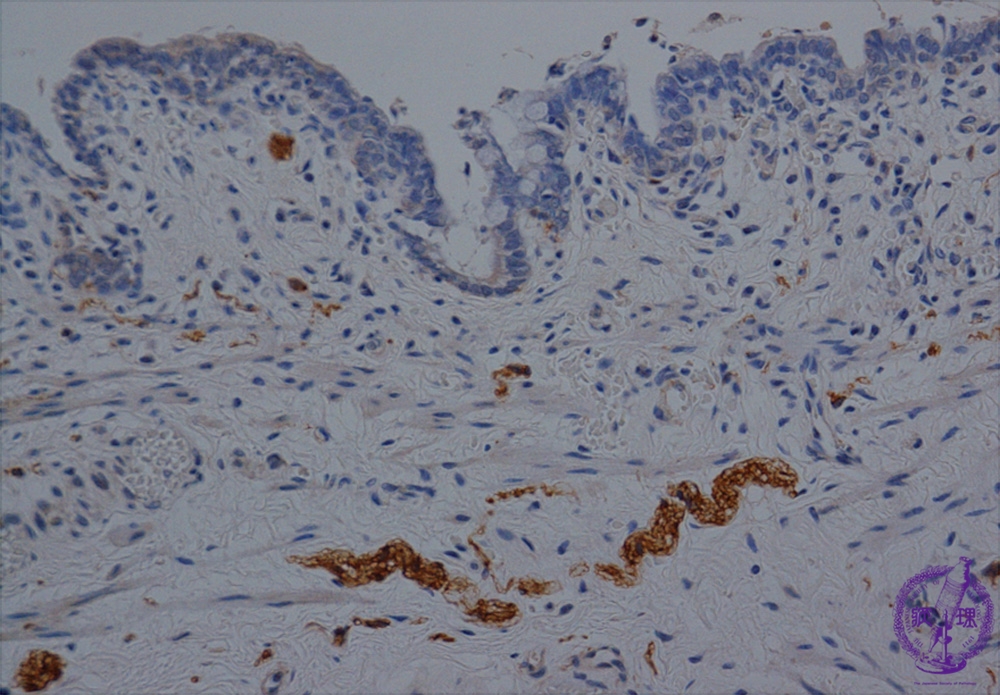

Microscopic view (Acetylcholinesterase stain): Acetylcholinesterase positive nerve fibers are observed in the submucosal layer.

Click the image to see the enlarged image.